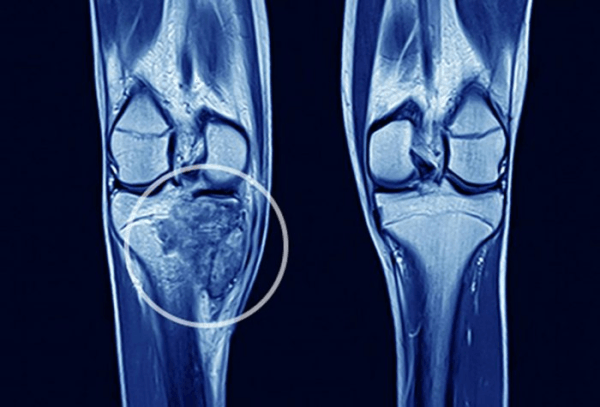

Những vị trí ung thư phổi di căn xương thường thấy bao gồm:

– Cột sống, đặc biệt là đốt sống ngực và bụng dưới

– Xương đùi và xương cẳng tay.

Ung thư phổi khi di căn có thể ảnh hưởng đến một số vị trí nhất định trong xương